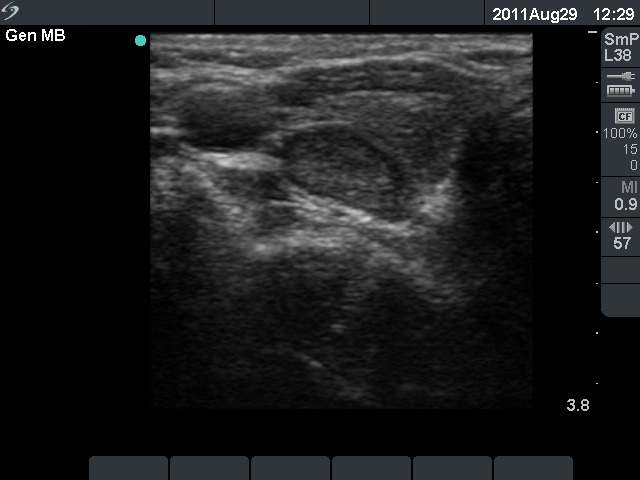

First examination (first row of images):

Clinical presentation: A 50-year-old woman was referred for evaluation of complaints suggesting hypothyroidism.

Palpation: Both lobes were firm.

Laboratory tests: TSH 23.7 mIU/L. Other results including serum calcium and phosphorus were in the normal range.

Ultrasonography: The thyroid was moderately hypoechogenic. There were two more hypoechogenic lesions in the dorsal part of the right lobe.

Aspiration cytology of the lesions in the dorsal part of the thyroid resulted in Hashimoto's thyroiditis.

Daily 75 microgram levothyroxine was given. We advised beside checking the TSH level, a follow-up ultrasound examination 2 years later.